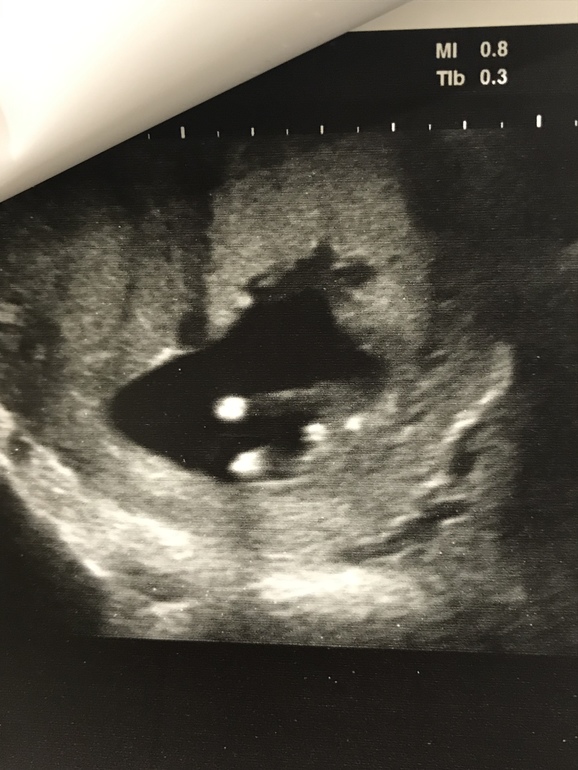

Самый не информативный ракурс 🌸потому что в 12 недель у них у всех между ног торчит если снизу смотреть ... по такому же снимку мне в 12,5 сказали 85% мальчик ... третий мальчик, Вы представляете что со мной было 🙈.. а в 17 недель уже сказали девочка .. спит сейчас моя доченька рядышком , ей уже 4 месяца 🤗

Вот мой мальчик на первом скрининге